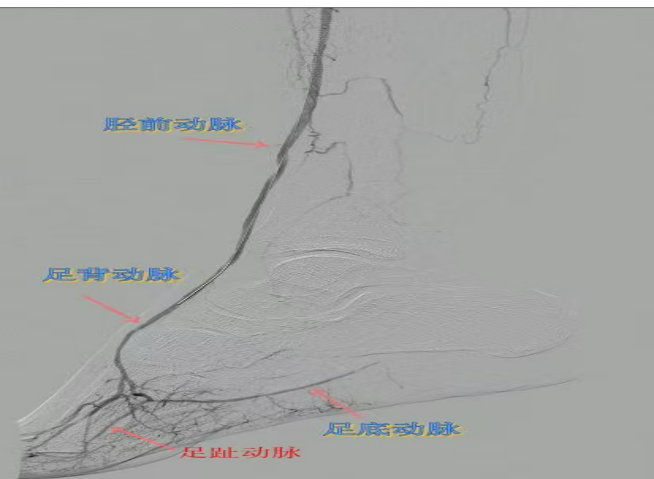

67岁女性患者,多年糖尿病、冠心病史,因右足溃烂伴凉麻疼痛长达2年就诊,此前曾接受外院介入术后血管再度闭塞。此次检查发现其股浅动脉、腘动脉至膝下血管全程闭塞,且伴有严重钙化。团队迎难而上,创新性经足背动脉逆向穿刺,耗时3小时成功贯通胫前动脉。术后当夜患者足部即感回暖,溃烂足趾疼痛显著缓解。术后结合中药外治(换药、熏洗、去腐生肌膏外敷)加速创面愈合。该患者已于出院,院外换药治疗。

影像检查:股浅动脉、腘动脉至膝下血管全程闭塞伴严重钙化。